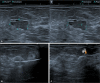

Figure 1

Patient with a core biopsy diagnosis of a fibroadenoma, initially measuring 1.2 cm, thereafter presenting growth and becoming palpable finding, growing to 2.3 cm by six months after diagnosis, when it was submitted to VAE. A: Pre-excision ultrasound showing the target lesion. B: Ultrasound during the procedure, showing the positioning of the needle below the lesion and activation of the vacuum. C: Post-excision ultrasound showing the clip marking the biopsy site. D: Macroscopic result of the fragments obtained from excision with a 7G needle.